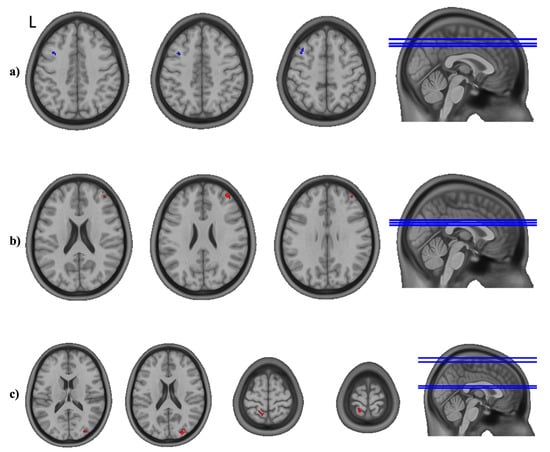

3.3. Seed-to-Whole-Brain Analysis

3.4. Post-Hoc Analyses